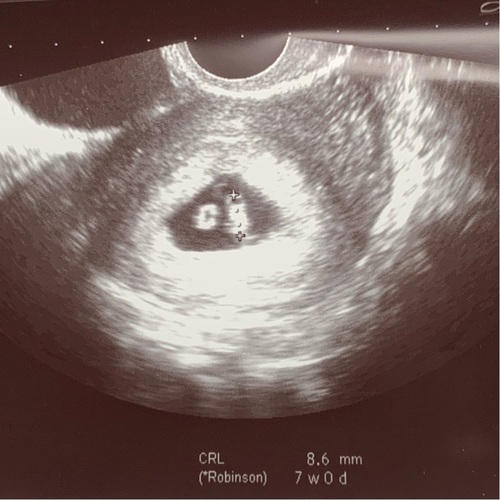

Hier onze echo met 7 weken. Links is de dooierzak, rechts de baby. Wij zagen echt een soort flikkerend lampje, dat was het hartje 馃グ Bij mij was het ook een inwendige echo, maar dat voel je amper. Stuk minder koud dan het echoapparaat op je buik in ieder geval 馃槄 hahaha

Dit is een echo van 7w wel niet de mijne is van een app. De echo is inwendig en je zal normaal een kloppend hartje zien.